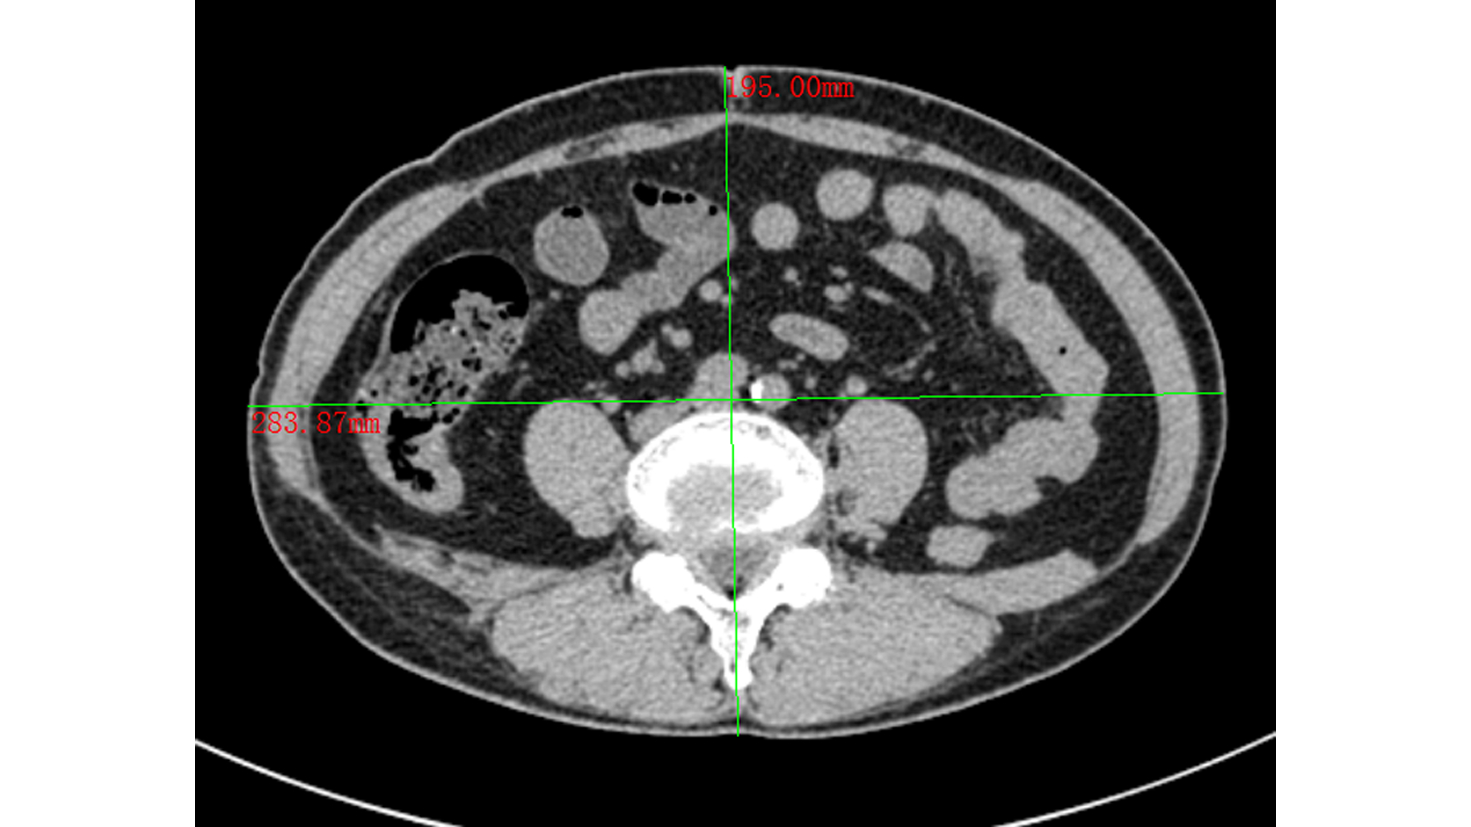

内脏脂肪相关指数与急性胰腺炎严重程度的关系

黄河铭, 杨慧莹, 覃颖颖, 唐国都

2022, 38(10): 2313-2319. DOI: 10.3969/j.issn.1001-5256.2022.10.021

摘要(986) HTML (347) PDF (2160KB)(97)

摘要:

目的  探讨内脏脂肪相关指数与急性胰腺炎(AP)严重程度之间的关系。  方法  选取2014年9月—2021年10月于广西医科大学第一附属医院住院的308例诊断为AP的患者作为研究对象,按AP分级诊断标准将其分为轻症急性胰腺炎(MAP)(n=186)、中度重症急性胰腺炎(MSAP)(n=60)和重症急性胰腺炎(SAP)(n=62),通过收集腰围、身高、体质量、血脂、生化等指标对比它们在年龄、住院费用及天数、评分系统和人体测量学指标等方面的差异。符合正态分布且方差齐性的计量资料组间比较采用单因素方差分析,方差不齐的组间及组内两两比较均采用Kruskal-Wallis H检验检验;不符合正态分布的计量资料组间及组内两两比较均采用Kruskal-Wallis H检验。分类资料和计数资料组间比较采用Kruskal-Wallis H检验。采用Spearman秩相关分析方法对各指标与AP的严重程度进行相关性分析;对各指标构建受试者工作特征曲线,并计算曲线下面积(AUC),比较AUC大小;用单因素及多因素Logistic回归分析方法找出MSAP和SAP发生的独立危险因素。  结果  住院费用及天数、TG、HDL-C、NLR、WBC、Alb、Cr、BUN、SIRS、BISAP、MEWS、Glasgow、PANC-3在3组间的差异均有统计学意义(P值均<0.05)。进一步两两比较发现,与MAP组相比,MSAP和SAP组的CMI、LAP、WTI、CVAI明显升高,差异均有统计学意义(P值均<0.05)。在相关性分析中,CMI与AP严重程度之间有一定相关性(r=0.352,P<0.001)。通过对各AUC大小的比较发现,CMI对预测MSAP和SAP发生的效能最大(AUC=0.708,95%CI:0.651~0.765,P<0.001)。单因素Logistic回归分析显示CMI、LAP、WTI、CVAI、WC是MSAP和SAP发生的危险因素(P值均<0.05),校正混杂因素后,CMI、CVAI是MSAP和SAP发生的独立危险因素(OR值分别为3.740、2.380, 95%CI分别为1.983~7.056、1.110~5.104,P值均<0.05)。  结论  内脏脂肪与AP病情严重程度有关;在4个内脏脂肪相关指数中(CMI、LAP、WTI、CVAI),以心脏代谢指数(CMI)在预测AP病情严重程度方面的价值最大,优于其他指数,两者呈正相关;CMI是MSAP和SAP发生的独立危险因素,或可作为预测和评估AP病情严重程度的潜在参考指标。